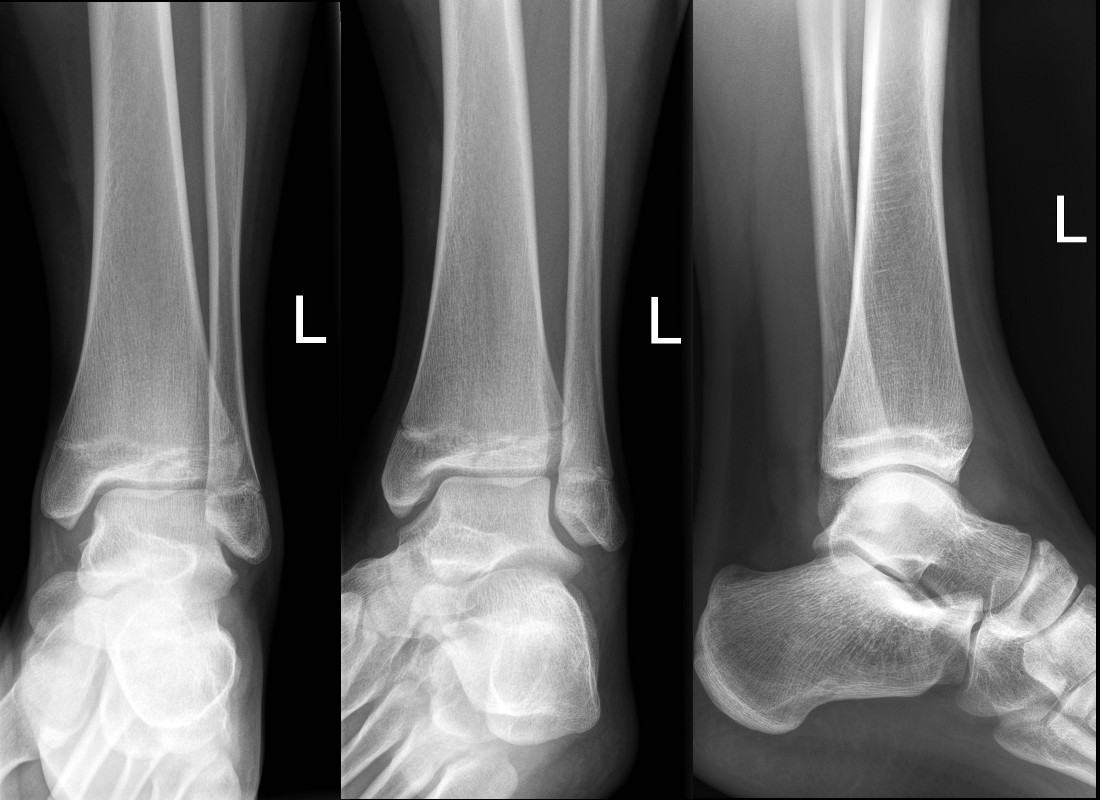

Minimally displaced Salter-Harris II fracture of the distal tibia

Minimally displaced Tilleaux fracture